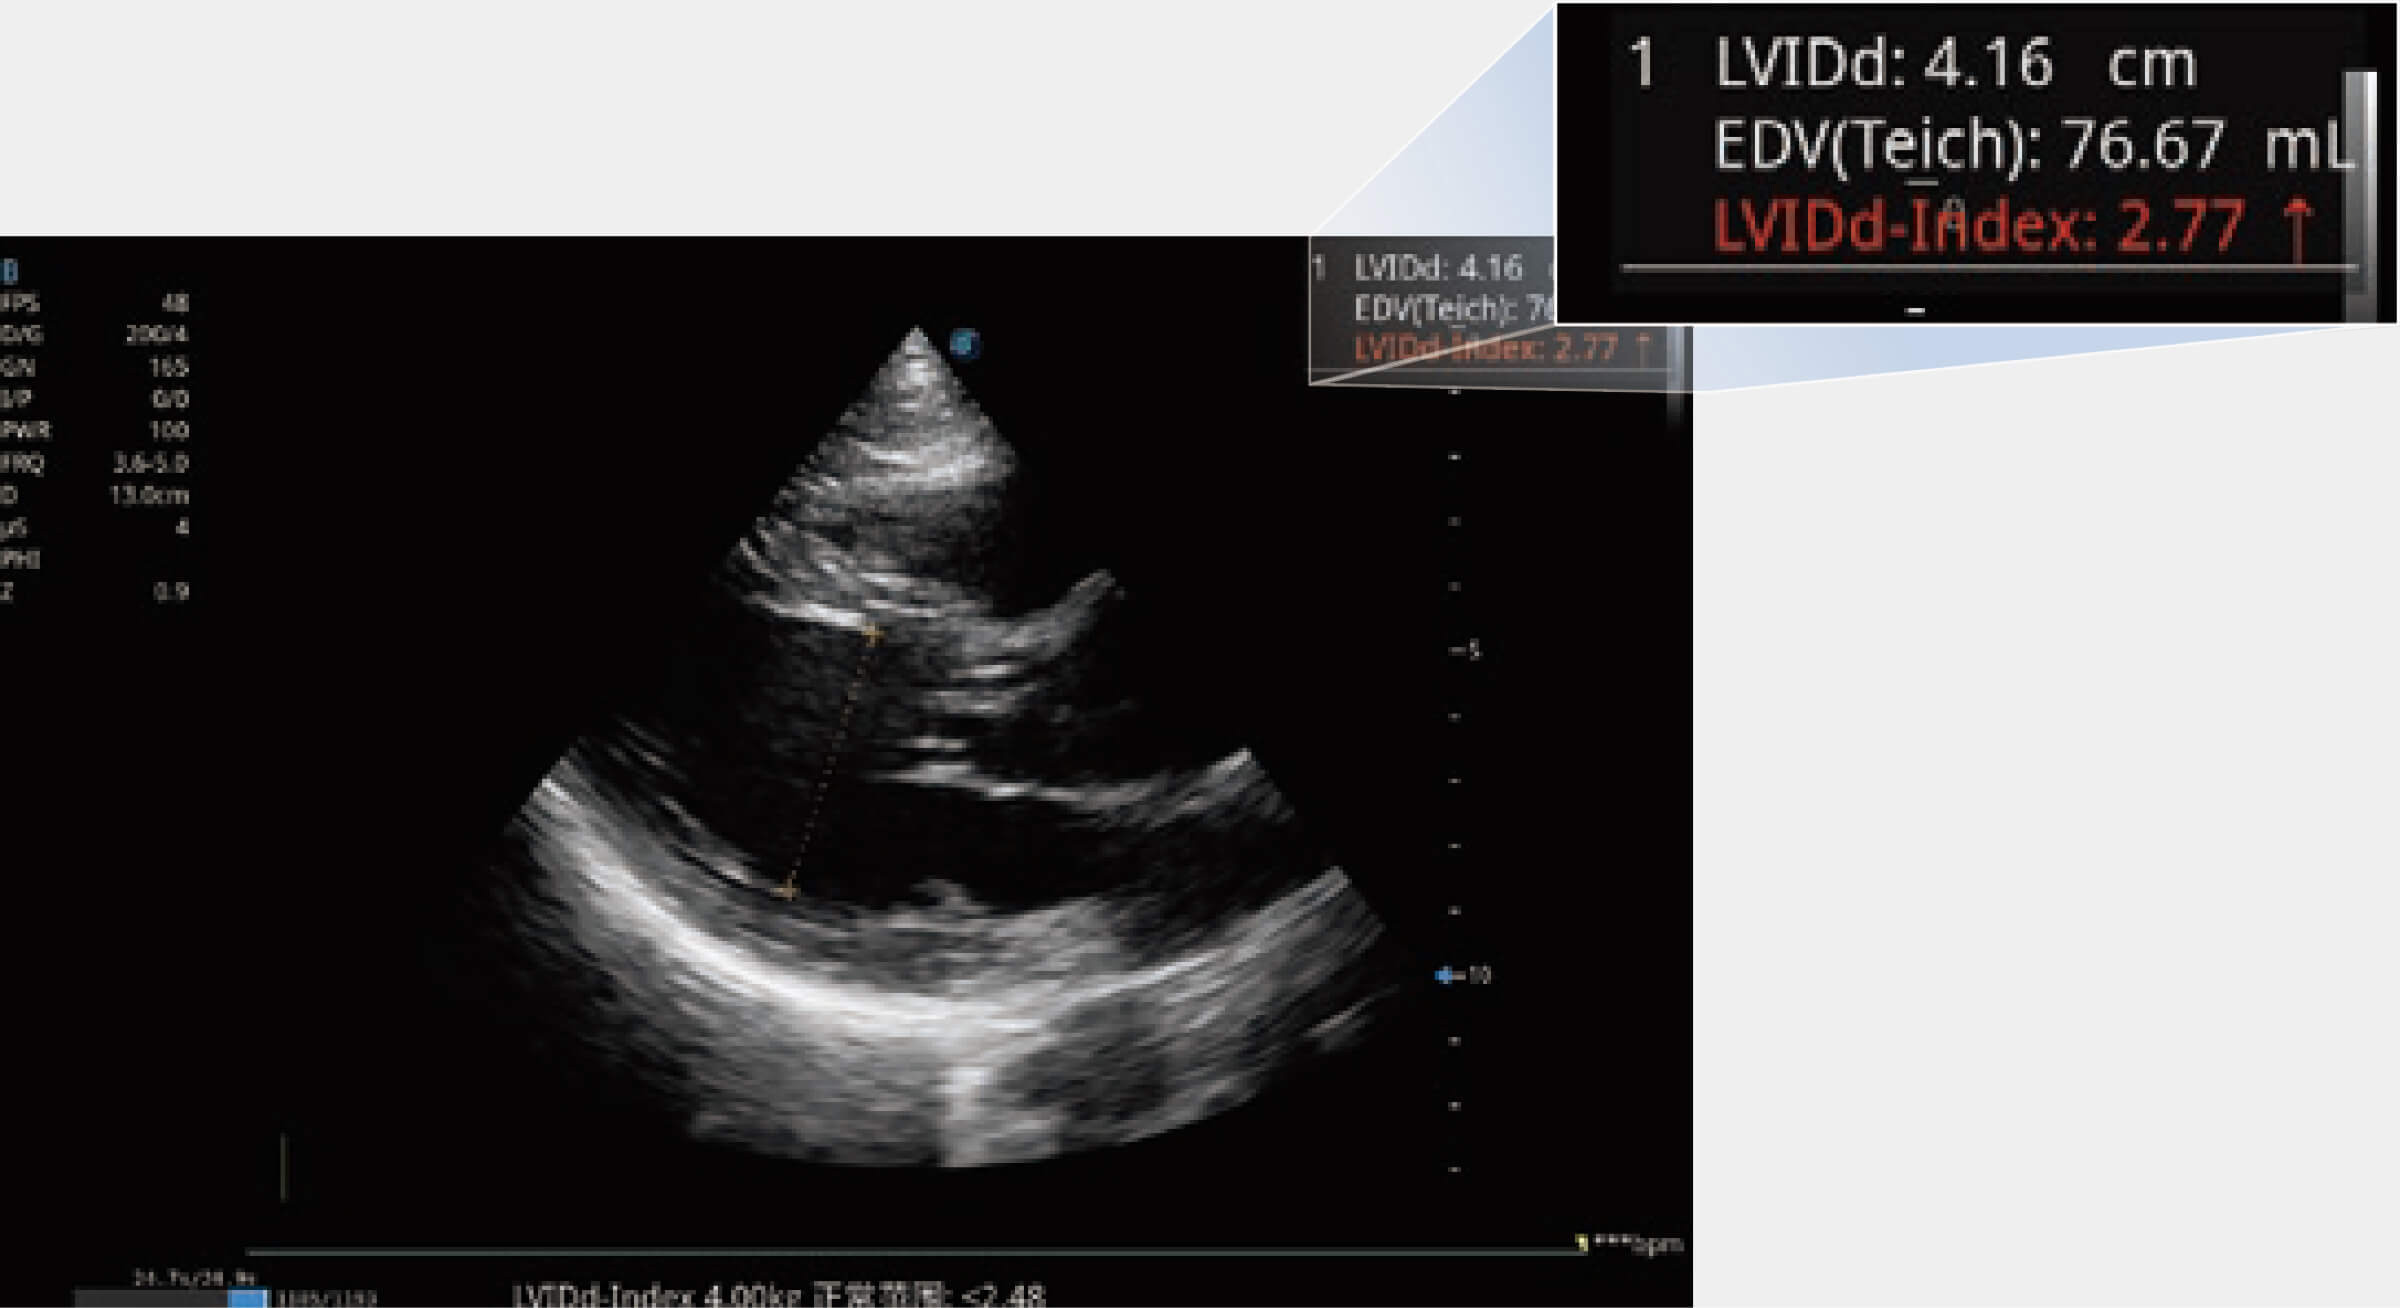

能夠基于左心室壁追蹤和辛普森法,自動計算射血分數(shù),支持多個可移動點描跡,與手動測量相比,極大節(jié)省了動物醫(yī)生的時間和精力。

當心臟測量結(jié)果超出正常范圍時,可實時預(yù)警提示動物醫(yī)生,減少疾病漏診概率。